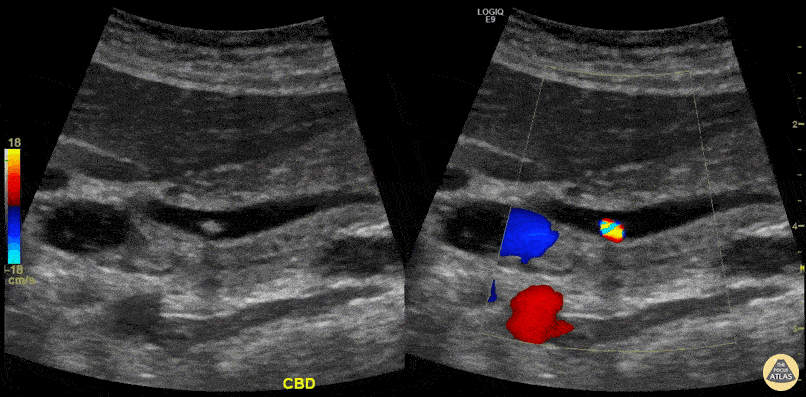

A patient presented with RUQ abdominal pain. Ultrasound showed cholelithiasis and choledocholithiasis. Left image shows a portion of the common bile duct containing a small hyperechoic shadowing mobile stone. Right image shows the same with color Doppler added demonstrating twinkling artifact. Learning point: Twinkling artifact is most often associated with urinary stones but also can be caused by gallstones (depending on composition), bowel gas, foley balloons, metallic objects, and many others. Twinkling artifact may help identify small stones that do not cause prominent acoustic shadowing. Michael Cover, MD @michaelc0ver